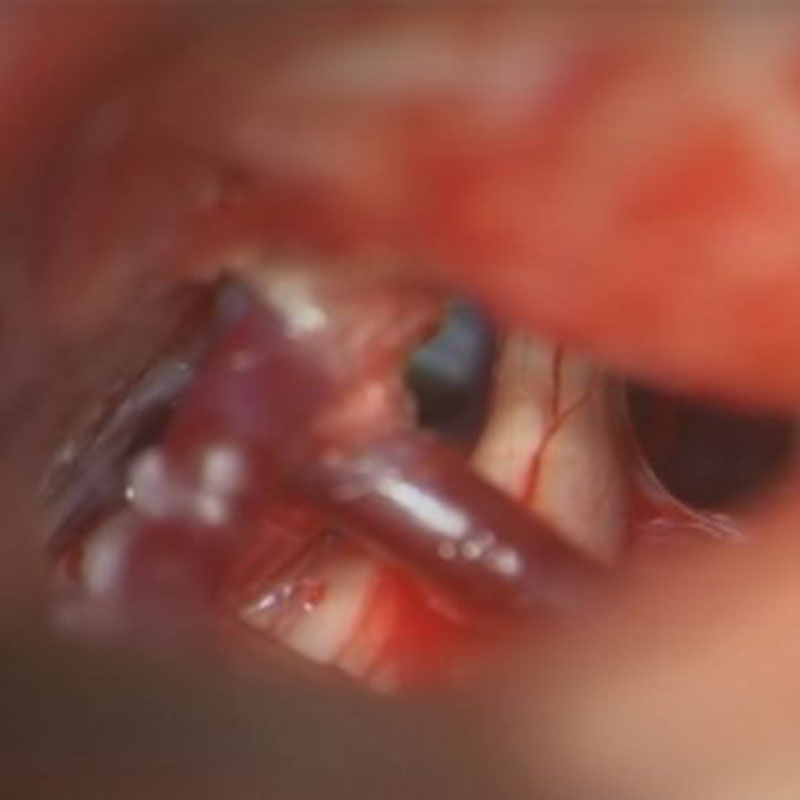

手術中

処置後